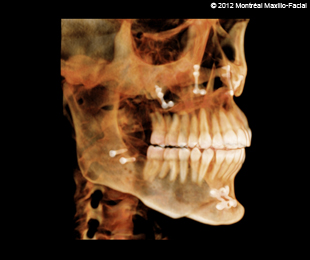

- Photos & radiographies